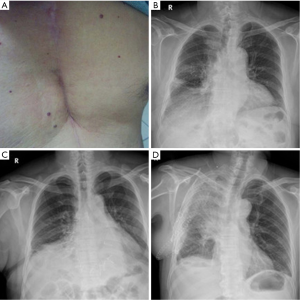

Titanium mesh was used when the defect in the chest wall was larger than 6 cm or ≥3 ribs. Before surgery, emission computed tomography (ECT), chest computed tomography (CT) scan (Figure 1) and pulmonary function tests were routinely used in all patients. The metastatic work-up was undertaken to eliminate an extrathoracic metastatic lesion. A total of 27 patients were identified, forming the basis of this review. Patients’ and tumors’ records were collected.

Double-lumen endobronchial tube was inserted following general anesthesia. The chest wall tumors and involved chest wall (including ribs and adjacent soft tissue) with at least 4 cm margin were totally removed (Figure 2). Subcutaneous tissue and skin were not removed. For relatively small resections, direct closure is performed, given that skin and subcutaneous tissue can be preserved with a good blood flow so that a titanium mesh can be safely covered. For lager defections, regional pedicled muscular or musculocutaneous flaps were used as choice for soft tissue coverage of the titanium meshes. Microscopic evaluation of the margins by frozen section was not routinely made due to wide resection. Titanium mesh prosthesis [Timesh (Flexmesh), Medtronic neurologic technologies] with tailored size was placed in the defect. Each side of the prosthesis overlapped the edge of the defect by 1-2 cm and was fixed with steel wires around the end of the resected ribs and/or sternum, as shown in Figure 1. The chest cavity was drained with a 28F chest tube. Subcutaneous drainage was not used in the mesh site. Pressure dressing was routinely used while not respiratory support postoperatively.

Table 4 summarized the postoperative follow-up course of all patients. The mean follow-up was 30.7 months (median 30.0 months, range, 4-62 months). All patients were seen every 3 months in the first year and then every 6 months, showing satisfactory cosmetic and functional outcomes (Figure 3A). During the course, none of the patients had experienced paradoxical respiratory motion or wound infection or skin necrosis. Furthermore, there was no mesh dislocation (Figure 3B-D). All patients performed VAS for pain measurement showed ‘excellent’ or ‘good’ outcomes points (median 3, average, 2.7). At the last follow-up, 23 patients were alive (19 with initially primary lesions and 4 with initially secondary lesions). Of those, two cases with local recurrence (one with fibrosarcoma and one with desmoid tumor) were observed at 52 and 27 months, respectively. Four died (two with initially primary disease including one with osteosarcoma, and one with sternal plasma cell tumors; two with secondary disease including one with Hodgkin lymphoma and one with squamous cell lung carcinoma). One died of both local recurrence and distant metastasis. Three cases of death were unknown. The 5-year DFS and OS of primary chest tumors was 72.1% and 80.8%, respectively (Figure 4).